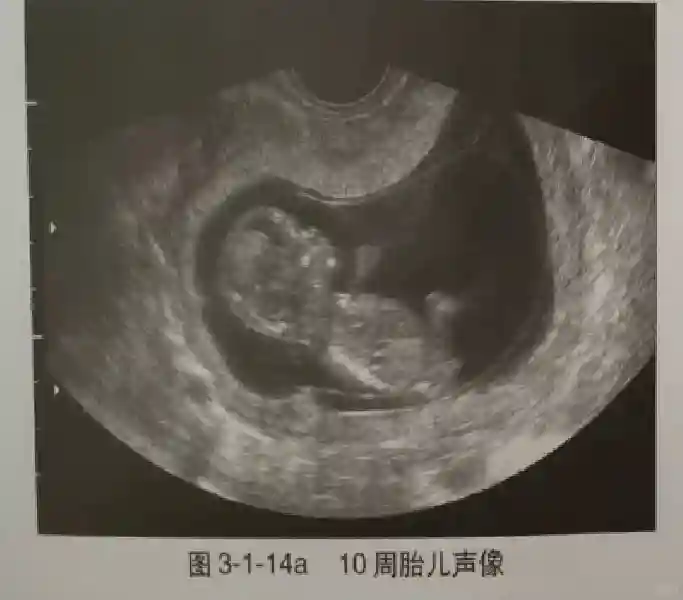

早孕早期建议采用阴道超声检查,以便早期了解胚胎发育情况,发现异常妊娠。早孕期超声是指从证实宫内妊娠到妊娠13+6周期间超声观察妊娠的情况,10周以前为胚胎,10周后为胎儿。

3??胚胎:胚胎通常在6-7周时可以为超声显示,起初为胎芽,表现为卵黄囊一侧局部组织增厚,达到1 -2 mm 时才有可能为超声测量出来。达4-5mm时可见胎心搏动,相应孕周为6-6.5周,妊娠囊大小为13-18mm。胚芽长度≥7㎜时仍未见心管搏动,提示胚胎停止发育。胚胎的出现和妊娠囊直径的关系:妊娠囊直径> 16 mm 时,经阴道超声应显示胚胎。妊娠囊直径> 25 mm 时,经腹超声均应显示胚胎。